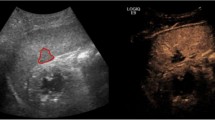

Spleen is the most frequently encountered organ injury in blunt abdominal trauma patients. Most splenic injuries can be treated conservatively, in the absence of absolute clinical indication for surgery at admission. However, delayed failure of nonsurgical treatment (bleeding) has been formerly reported in 10–31% of cases [8] and may occur up to 10 days (or even later) after trauma. A major improvement in the non-operative management of blunt splenic trauma patients was achieved when two major observations were reported in the scientific literature. Firstly, an association was established between the presence of intrasplenic vascular injuries at CT and an increased risk of delayed bleeding [9]. Secondly, the angiographic embolization of these vascular injuries has been associated with a significant drop in the rate of unsuccessful non-operative management (from 13% to 6%) [10]. Based on these observations, the classical AAST-1994 surgical splenic injury scale classification, only based on morphological criteria, was completed by a CT-based classification initially proposed by Stuart Mirvis [11] and slightly reshuffled in 2018 [12]. This classification takes into account vascular lesions (pseudoaneurysms, arteriovenous fistula or active bleedings) confined within the spleen (Fig. 1.1) and those extending beyond the spleen (active bleeding). Vascular splenic lesions appear at CT as focal blush of contrast with an attenuation close to arteries and greater than that of the spleen parenchyma. Delayed CT images must be systematically obtained in the presence of a vascular lesion to differentiate those that vanishes (pseudoaneurysms and arteriovenous fistula) from those which stay and expand (active bleeding).

Whether a systematic follow-up imaging patients should be performed in hemodynamically stable blunt splenic trauma patients remains a yet unsolved question. It has been reported that a majority of traumatic splenic pseudoaneuryms (38%–74%) would only be detected on control CT performed within 24–72 h after admission [13]. For practical reasons, most of the trauma associations do not recommend a systematic delayed CT in hemodynamically stable splenic trauma patients. With a reported 75% sensitivity and 100% specificity for detection of delayed splenic pseudoaneurysms (in skilled hands), bedside contrast enhanced sonographic examination has been advocated as a good option in this setting [14].